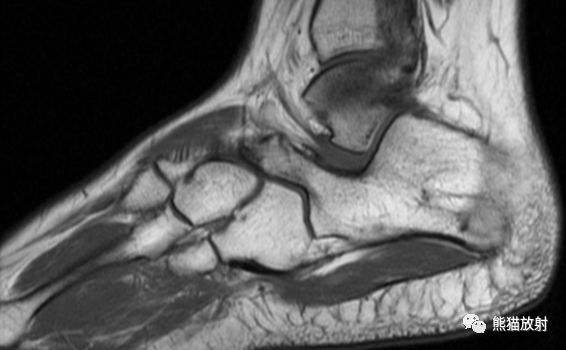

先看一个病例:患者,男性,16岁,足部疼痛。

MR矢状PD压脂、矢状T1WI;主要表现:跟骨和舟骨之间可见骨性联合,MR上相应区域无水肿

食蚁兽鼻征

1、足侧位X线片上。

2、食蚁兽的鼻子:跟骨的前上部管状伸长,接近舟骨或与其重叠。

3、提示跟舟联合

跟舟联合在侧位X线片上呈现食蚁兽鼻征,拍摄45°内斜位X片观察跟舟联合